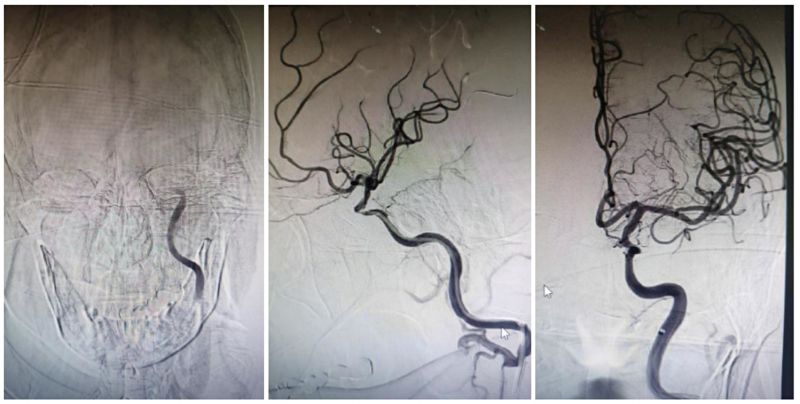

那天正当休息日,介入医学科副主任医师柳海华、主治医师宫玉、介入手术室护师李佳凯、介入技师刘静接到通知后,迅速赶到北院区介入手术室,立即给于女士进行脑血管造影评估,并进行了急诊血管再通治疗。1小时过后,于女士已经闭塞的左侧颈内动脉被顺利开通。

左图显示左侧颈内动脉虹吸段以远闭塞;中图显示导丝导管通过后,左颈内虹吸段管腔重度狭窄;右图可见支架置入后左颈内动脉再通。